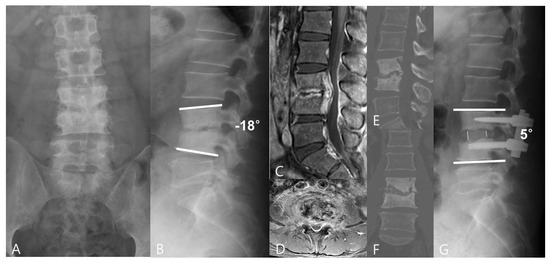

3.2. Radiographic Outcomes